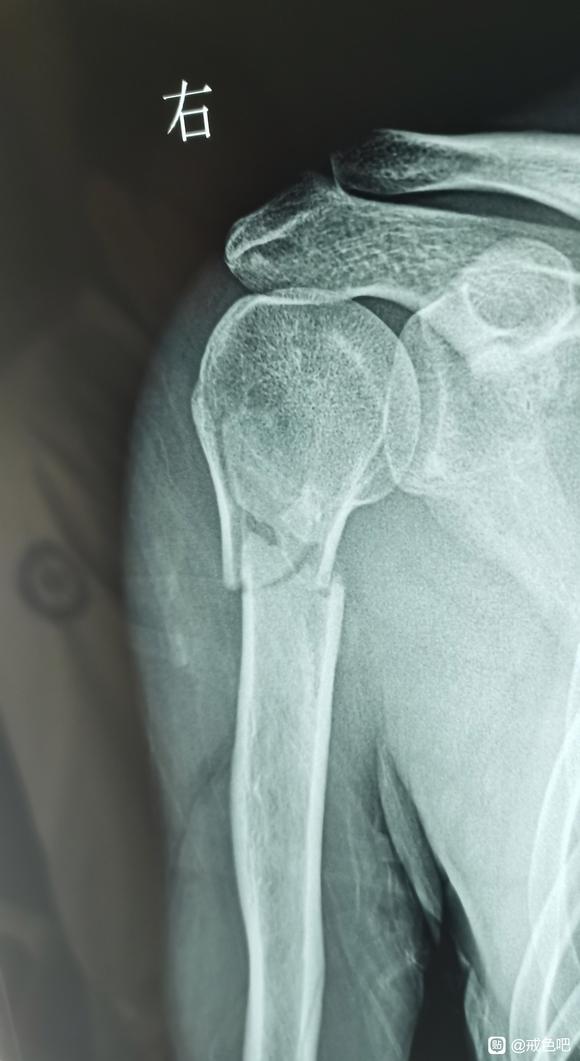

过了一个多月我就得了大恶报,我陪孩子踢球时把胳膊摔断了,当时我以为只是脱臼,而且正有疫情,小区封了出不了门,六点多医院也下班了,不知道是断了以为只是脱臼,就在小区里找了一个写着正骨的地方复位,复位时将胳膊抬起,用力一拖,虽然很疼还可以忍受,脱臼复位后轻松了些,只能动一点,他拿起我的胳膊想捋一下筋,因为不知道断了,一拎起来感觉断的地方痛入骨髓,痛的昏天黑地,见我痛的大叫就放下了,他说是筋伤了需要慢慢恢复,我就回家慢慢养。回家后睡觉只能穿着衣服半躺着,躺累了,稍微翻一点身都疼痛难忍。过了几天,我妈让我去医院拍片看看。在居委会开了看病的出门条,去附近的医院拍了片子,拍之前以为最多只是骨裂,没想到是粉碎性骨折。医生说要做手术打钢板,我问了一位认识的骨科专家说移位不大,恢复好位置后打石膏就可以,因为动手术要做两次,现在做手术打上钢板,一年后在做手术把钢板取出,疫情进不了京,所以就在家等疫情解封后再去治。在家里等的这段时间,食不知味,寝不能安,衣不能解,困极睡会,半夜醒来,如在炼狱,手肿的像馒头,打下喷嚏,震到断骨的地方,能把眼泪疼出来。做的恶事报应没成熟时,感觉生活一片祥和轻松惬意,报应成熟来到时,那真是痛苦难忍,度日如年,需要受的苦头想少一分都难。在家熬了十天左右,丝毫没有解封的意思,就去附近的医院做了手术。打了十根钢钉,缝了几十针,做手术时医生说我这一下摔的够重的。从摔断到治疗一波三折受三次罪,去正骨受一次罪,刚好疫情出不了门在家熬着受一次罪,做手术又受一次罪。做了大恶遭报应惩罚时真是痛不欲生,如在炼狱。